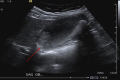

Gallbladder Carcinoma, the Difficulty of Early Detection: A Case Report

Gallbladder carcinoma (GBC) is an uncommon malignancy with a high mortality rate. Detecting gallbladder carcinoma in its early stages can be difficult, despite improvements in ultrasound and computed tomography (CT) imaging. Most diagnoses of GBC are made at advanced stages, with the majority being found incidentally during surgery for cholelithiasis. The presented case demonstrates the difficulty of diagnosing GBC preoperatively in its early stages.